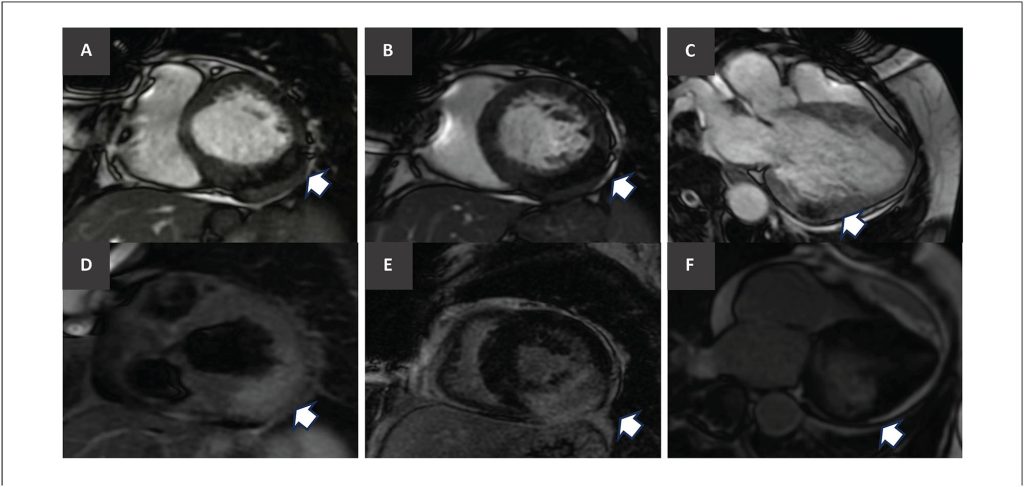

Intramyocardial Cardiac Tumor: A Case Report

Primary cardiac tumors are rare entities, approximately 75% of which are benign, with myxoma as the most common type., Only about 15% of primary cardiac tumors are malignant, predominantly sarcomas. In contrast, metastatic cardiac involvement is relatively frequent and has been identified in up to 9% of patients who died from cancer.

Clinical manifestations are more closely related to tumor location than to histopathological classification. They may result from embolic phenomena, intracardiac obstruction with signs of heart failure (HF), valvular involvement, myocardial invasion with alterations in contractile function and electrical conduction, and pericardial involvement with the risk of effusion and cardiac tamponade, among other presentations.